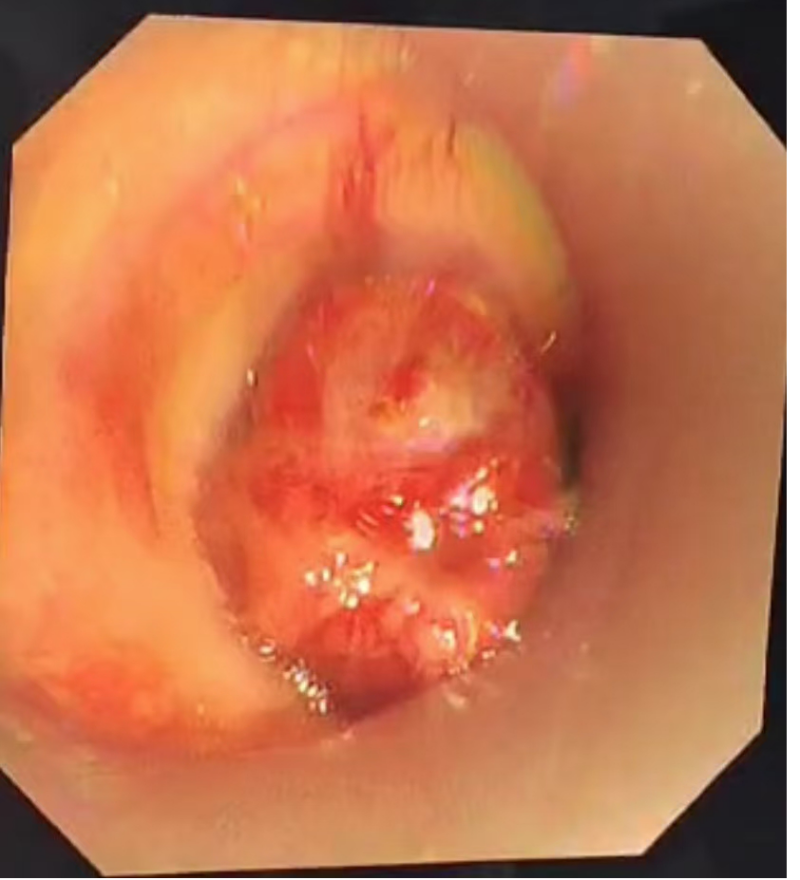

看着黄先生痛苦不已,家属心急如焚,打听到自治区南溪山医院院呼吸与危重症医学科二病区有神奇的呼吸介入手术可缓解呼吸困难,遂于春节期间紧急转至该病区。屈东明博士查看资料后迅速组织完善术前检查,呼吸介入团队联合麻醉科、内镜中心联合制定个性化方案。在全麻下行沙漏型硅酮支架植入术,术中发现患者情况更为严重,因肿瘤侵犯气管扭曲,鞘管无法通过最狭窄部位,同时支架推送器也无法通过鞘管。呼吸介入团队经过商量后迅速调整手术方案,终于成功植入气道支架,患者从“命悬一线”到自由呼吸!